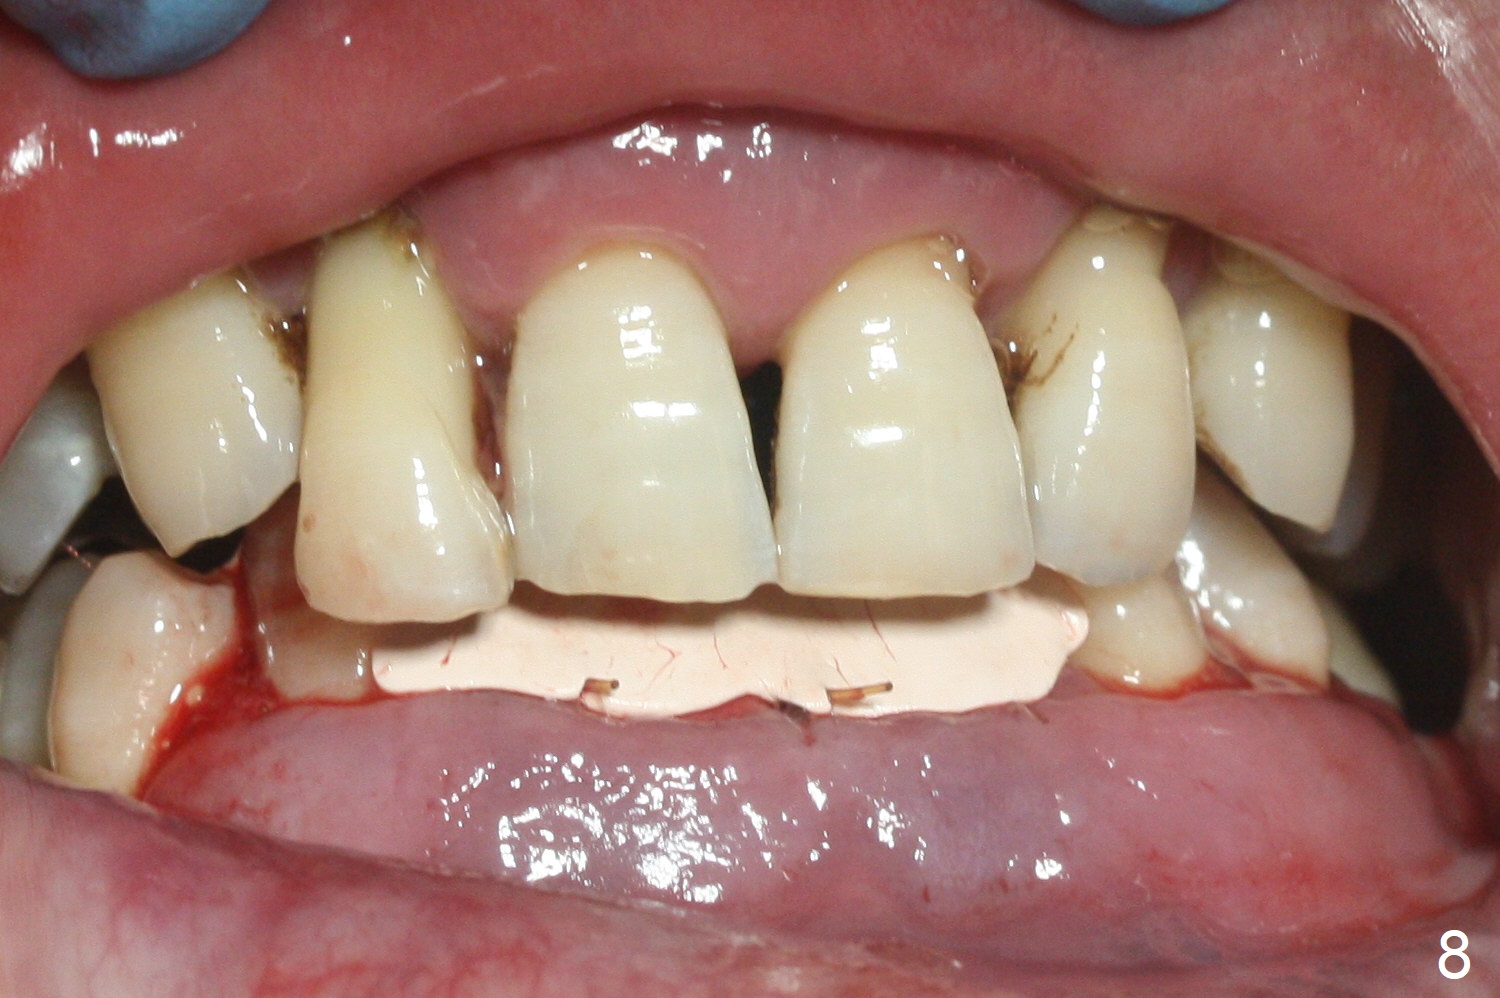

After extraction of 4 of the lower incisors, there are basically 2 sockets (#23/24 and 25/26), separated by the apparently midline bone (Fig.1 red line).  In spite of using Lindamann bur to move the 25/26 osteotomy mesially, a 3x14(2) mm dummy implant remains close to the tooth #27 (Fig.2).  The terminal branch of the Incisive Canal (<) is located between the lateral and central incisors.  A de novo osteotomy (Fig.3 (1.5 mm drill)) is made mesial to the original one (O).  While the 3x14(2) mm dummy implant is incompletely placed at #25/26, a 3x14(4) mm 1-piece one is placed at #23/24 (Fig.4).  Finally the same implant is placed at #25/26 with placement of mineralized cortical/cancellous bone (Fig.5 *).  When the large sockets are sutured, the supraerupted teeth #7-9 touch the lower gingiva (Fig.6).  The incisal edge is reduced for clearance (Fig.7).  Periodontal dressing is less likely to be dislodged with the incisal edge reduction (Fig.8,9).  A provisional FPD is fabricated 1 week postop.  Hard (Fig.10) and soft (Fig.11,12) tissues heal 5.5 months postop.  The patient returns for crown cementation 3 months post impression (9 months postop, Fig.13,14).